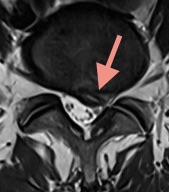

腰部椎間板ヘルニアの手術前MRI画像 矢印は脱出したヘルニアを示しており、神経を圧迫している